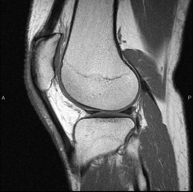

Exploració per estudiar lesions a l'articulació, com trencaments dels meniscals i dels lligaments creuats (únicament es poden detectar amb aquesta prova), condropatia o desgast del cartílag i moltes altres alteracions derivades de l'activitat esportiva i dels canvis degeneratius (osteoartrosi). La durada aproximada és de 18 minuts. No utilitza radiació ionitzant. - RM de Cama